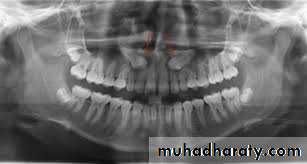

• Resorption of the second molars (rare). • Preparation for the provision of prosthesis. OPG is the radiograph of choice. Periapical view, although it produces more detailed image, maybe unsatisfactory because of the angle of projection.

• OPG; can be used to localize impacted canine on the basis that palatally impacted canine appear magnified. It can also demonstrate the vertical angulation and its height.